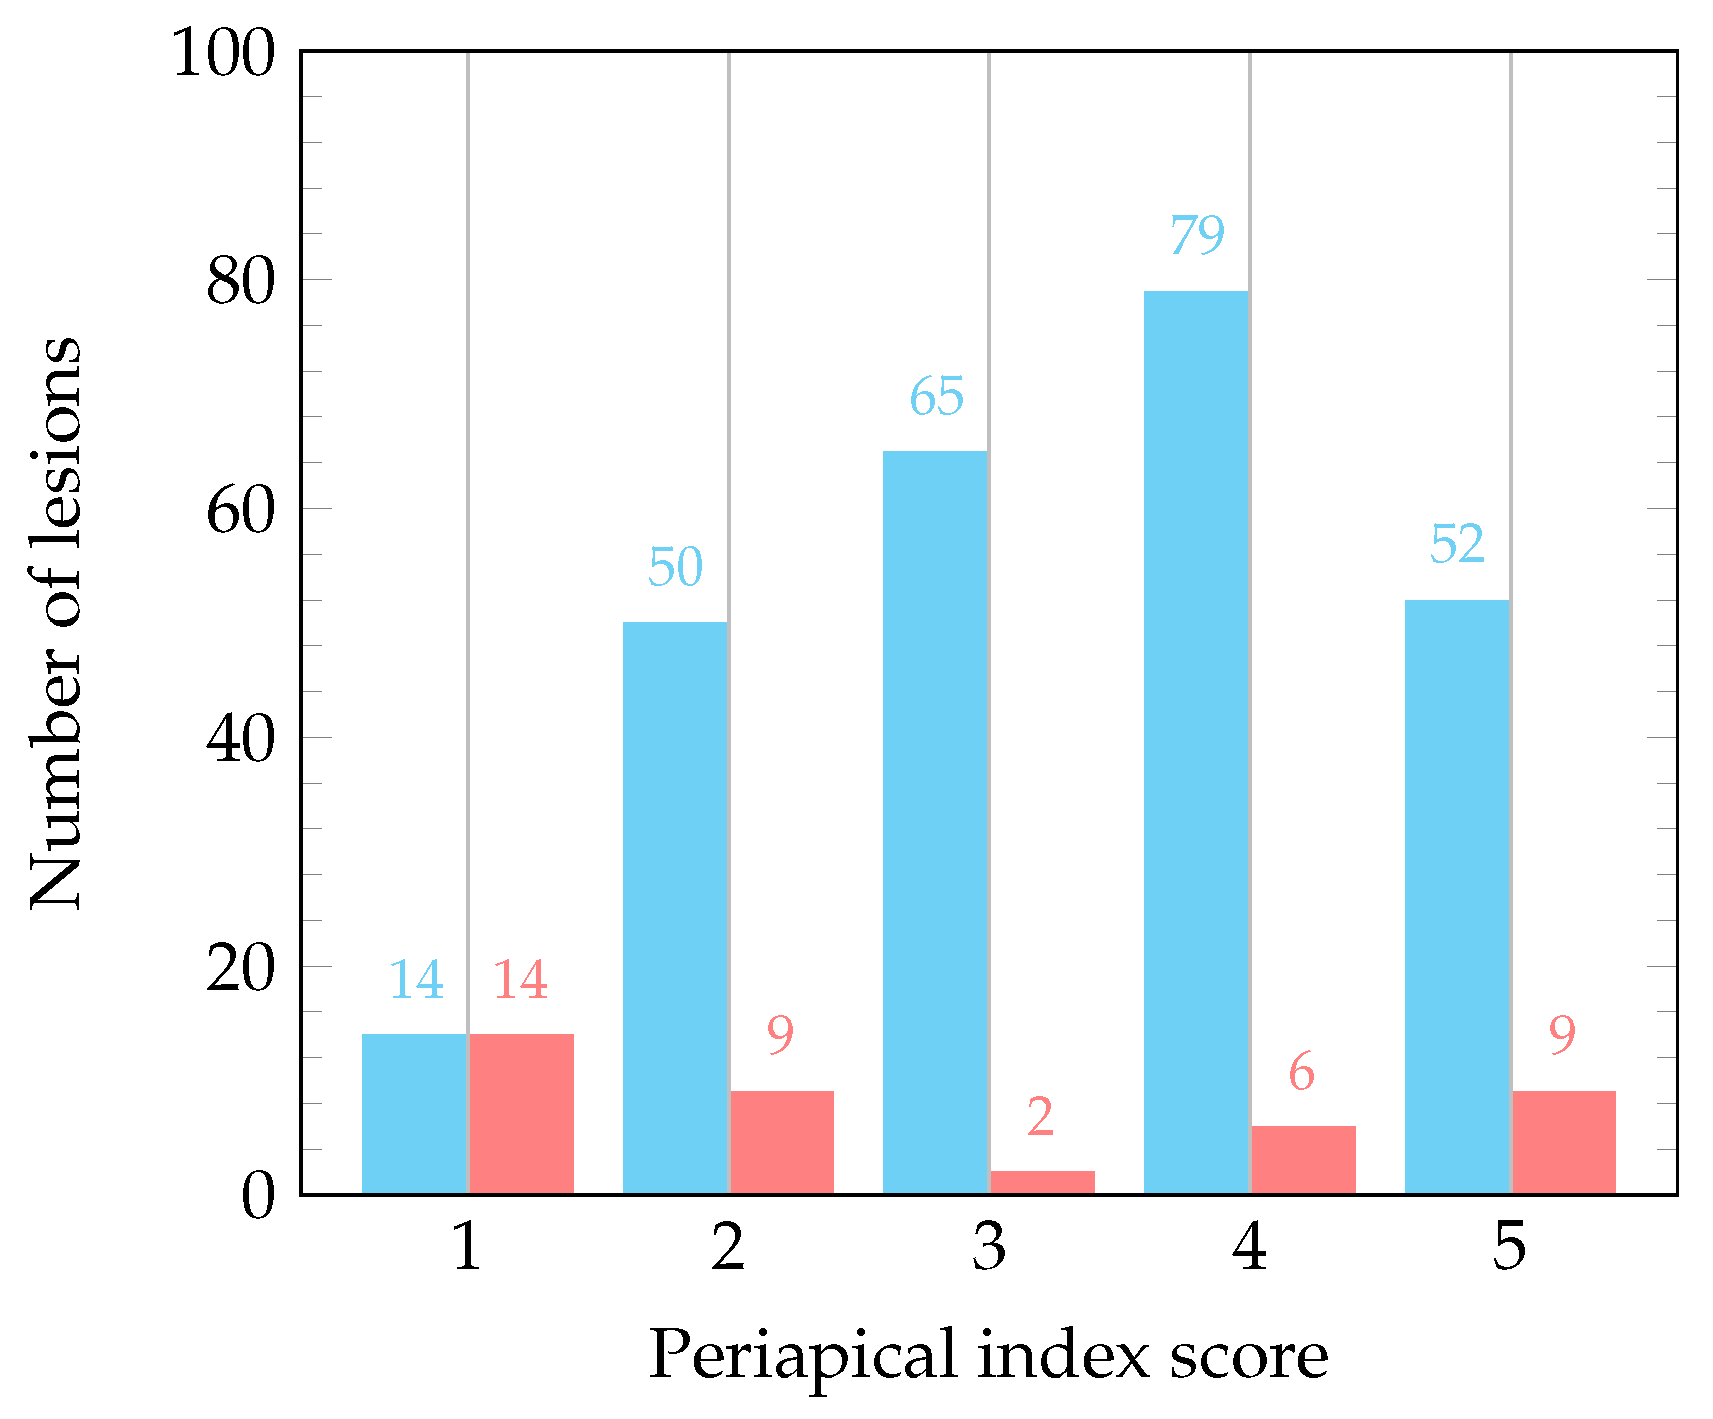

| Lesion classification 1 | Score 1: 28 ( 9.3%) | Diameter > 0.5–1 mm |

| Score 2: 59 (19.7%) | Diameter > 1–2 mm | |

| Score 3: 67 (22.3%) | Diameter > 2–4 mm | |

| Score 4: 85 (28.3%) | Diameter > 4–8 mm | |

| Score 5: 61 (20.3%) | Diameter > 8 mm |